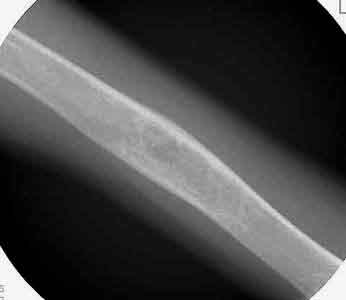

Die 14-jährige Patientin erlitt mit 12 Jahren eine pathologische Oberarmfraktur durch eine juvenile Knochencyste. Diese wurde konservativ behandelt. Nach der Ausheilung der Fraktur war die Cyste zwar etwas kleiner geworden, bestand aber weiterhin. Die Corticalis blieb aber papierdünn und damit frakturgefährdet. Man entschloß sich im Jahr 1998 (siehe Bild) weiter abzuwarten.